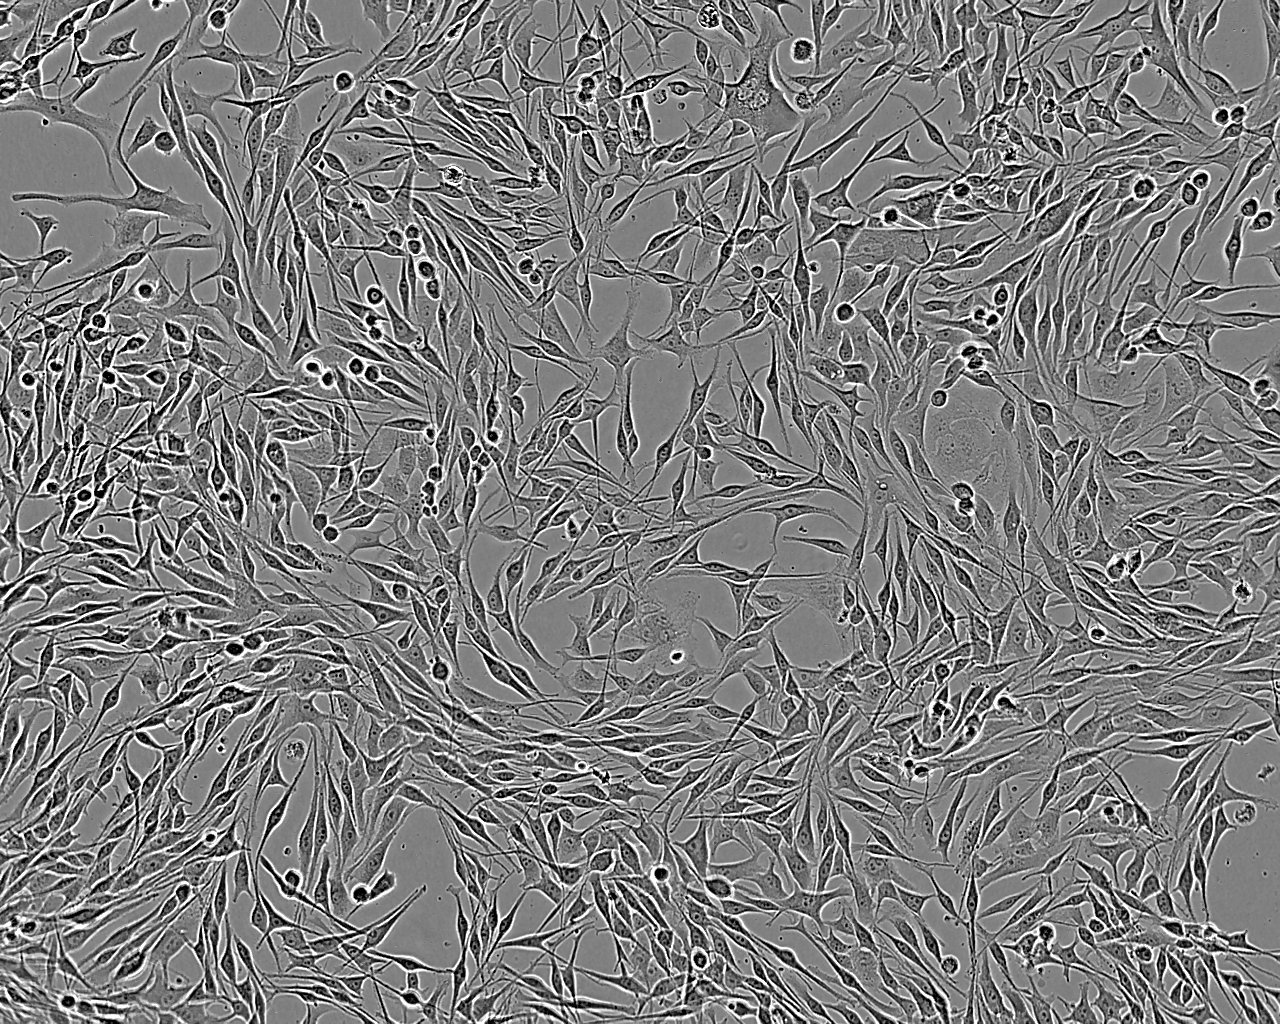

Derived from a brain metastasis of a 62 year old male with melanoma. The cells bleb during culture.

Images